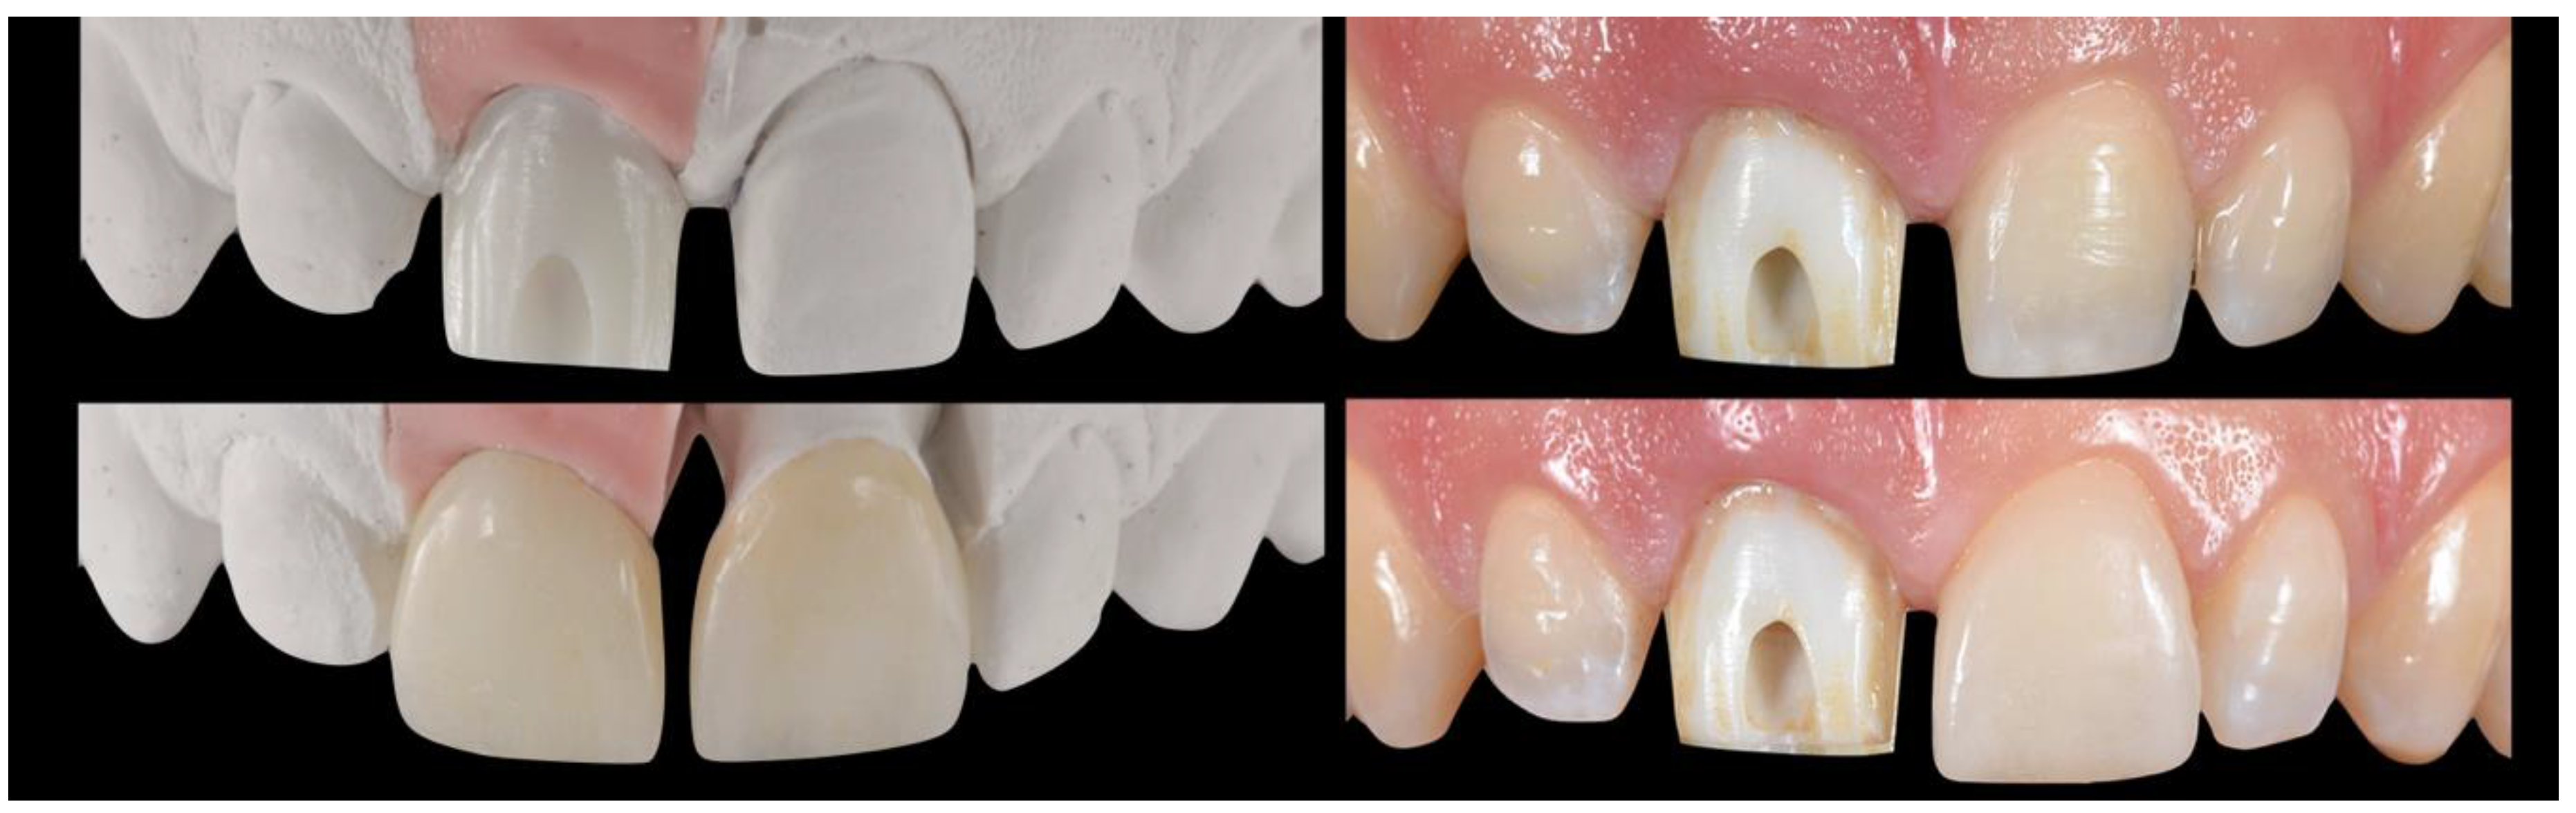

2.6. Lab Stage

2.7. Prosthesis Delivery